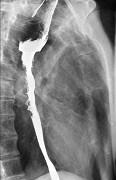

问题 女性患者,67岁,进行性吞咽困难半年,X线及CT检查如图,应诊断为()

选项 A.食道癌 B.食道憩室 C.食道炎 D.食道良性狭窄 E.食道静脉曲张

答案 A